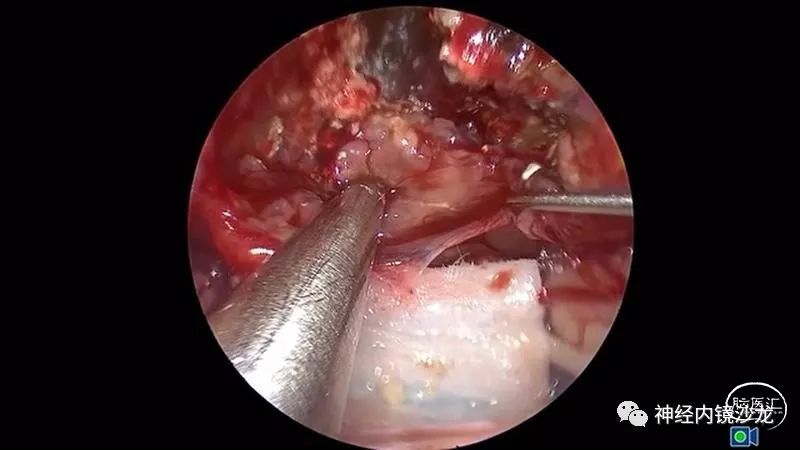

手术暴露充分术野,从蝶骨平台到斜坡,从眼眶到眼眶。切除大块钙化部分肿瘤后,我们找到肿瘤包膜和下丘脑、视觉通路之间的清晰的分离平面。切除结束时,发生了后交通动脉从大脑后动脉撕脱导致的动脉出血。采用单轴持夹器放置一个成角的动脉瘤夹,以夹闭损伤部位并保证供血动脉不狭窄。术后即刻和晚期磁共振成像和CTA检查显示肿瘤全切、无卒中、无假性动脉瘤形成。